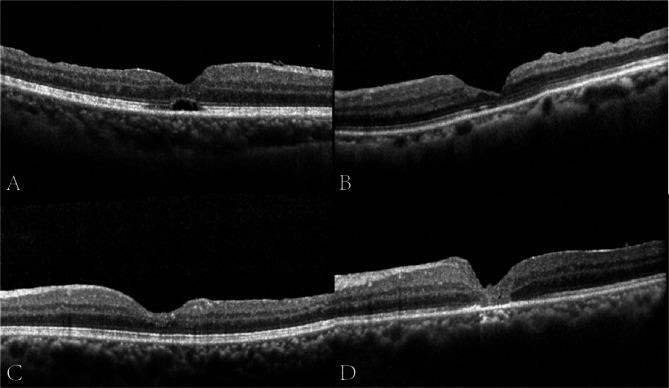

At 6 months postoperatively, MH closure was achieved in 24/27 patients in Group A and 22/27 patients in Group B (88.89% vs. 81.48%, P = 0.704) with U-shaped closure rates being significantly higher in Group A (P = 0.029). The average BCVA at month 6 was 0.69 ± 0.38 (LogMAR) in Group A and 0.91 ± 0.39 in Group B (P = 0.015) with the improvement in BCVA being significantly higher in Group A (0.50 ± 0.59 vs. 0.31 ± 0.59, P = 0.045). The recovery rates of ELM were significantly higher in Group A (P = 0.026).

Our three-step approach greatly improves anatomical and functional outcomes compared with IFT. This novel surgery has a dominant advantage in earlier and higher ultimate closure rate, U-type closure rate, and ELM recovery rate, and more importantly, better recovery of BCVA.

术后6个月时,A组24/27例患者黄斑裂孔闭合,B组22/27例患者黄斑裂孔闭合(88.89%对81.48%,P = 0.704),A组U形闭合率显著更高(P = 0.029)。A组6个月时平均BCVA为0.69±0.38(LogMAR),B组为0.91±0.39(P = 0.015),A组BCVA改善显著更高(0.50±0.59对0.31±0.59,P = 0.045)。A组外层限制膜(ELM)恢复率显著更高(P = 0.026)。

与IFT相比,我们的三步法极大地改善了解剖学和功能学结果。这种新型手术在早期和更高的最终闭合率、U型闭合率和ELM恢复率方面具有显著优势,更重要的是,能更好地恢复BCVA。